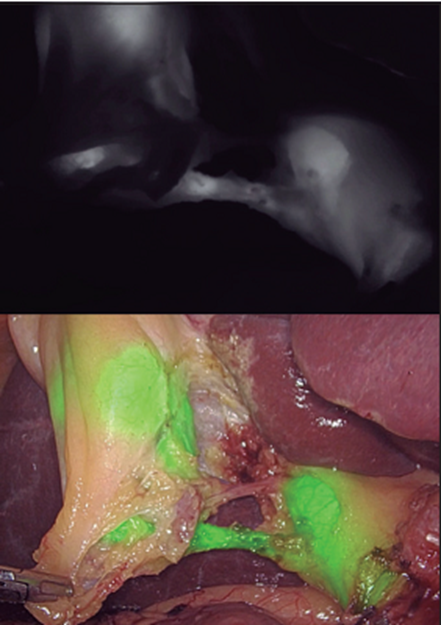

Figure 5 :The use of indocyanine green is observed during the dissection.

Use of indocyanine green (VI): Indocyanine green (VI) (Fig. 5) is a tricarbocyanine pigment that is administered intravenously and quickly and completely binds to albumin and is taken up by hepatocytes and eliminated for the bile. It has been approved by the FDA and among them for fluorescence-guided surgery (F). The first to use it to identify the bile duct was Ishizawa, as reported by Pérez et al.(32).  There are experimental works that demonstrate that indocyanine green reaches a peak of F in the bile 8 minutes after its administration and this F is due to the fact that it binds to proteins present in the bile. It can be observed in the bile duct as early as 15 minutes after administration and F in the bile duct can persist more than 7 hours after administration. One of the problems is the penetration of light, which is not greater than 10 mm, so it can be difficult to identify structures with this technique in situations of inflammation. Identification of biliary anatomy is one of the most established applications for one simple reason: indocyanine green has an exclusively hepatic metabolism and excretion begins within 30 minutes after injection. We will comment on its use in LIVB, recently a series of possible advantages of the use of fluorescence cholangiography with indocyanine green (CFVI) have been postulated such as: a) It saves time. b) Prevents injuries associated with conventional IOC. c) The technique is more convenient as it requires only a preoperative intravenous injection of indocyanine green and fluorescent images obtained in real time at any time during surgery without the need for radiation. d) Allows surgeons to evaluate the extrahepatic bile duct easily and in a short period of time. e) It is a safe procedure.

Pujol et al.(33) compare fluorescence cholangiography with intraoperative cholangiography in a group of 82 patients undergoing laparoscopic cholecystectomy and found that the identification of biliary anatomy was greater and faster with CFVI. In 20 patients where IOC could not be completed, in 80% identification was achieved with indocyanine green. Indocyanine green cholangiography failed to identify any biliary structure in less than 5% of cases. Catalin et al.(34) analyzed the usefulness of CFVI in 65 patients undergoing laparoscopic cholecystectomy. They perform fluorescence before and after the dissection of Calot's triangle and determine in which patients the cystic duct and bile duct are identified and also correlate it with cholangioresonance images. In the randomized multicenter study by Van Den Vos et al. (35) to determine the effectiveness of indocyanine green in determining the drawing of the safety window during laparoscopic cholecystectomy, which should offer answers regarding the effectiveness of the technique and the doses used. In this sense, an interesting work by Ambe et al.(36), in which they compare different moments and different doses of administration, concludes that a dose of 0.25 mg/Kg administered 45 minutes before facilitates the safe intraoperative identification of the biliary tree. and considers that fluorescence cholangiography is a safe and effective practical method of identifying the bile duct. Kontantinos et al. (37) determined that it is much cheaper than IOC ($778 vs. $14), much faster (consuming 10 times less time), easy to perform by surgeons, and at least as effective as IOC.

In our country there is no report of its use, nor experience considering it as another work tool to achieve a safe procedure, although there is still no uniform use of the VI. Furthermore, its use is limited during acute episodes of the extrahepatic bile duct or when a stone is lodged in the cystic duct. Furthermore, it has no use for the diagnosis of choledocholithiasis, although its introduction in bile duct surgery is not this. Where IOC continues to be of choice in the aforementioned for Pucher el al.(1) in SAGES expert Delphi consensus: critical factors for safe surgical practice in laparoscopic cholecystectomy.